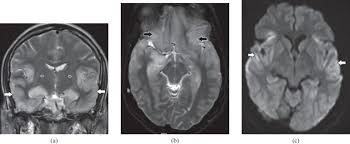

Diffusion Imaging In Brain Infections Radiology Key

Diffusion Imaging In Brain Infections Radiology Key from radiologykey.com

Two subtypes are recognized which differ in demographics, virus, and pattern of involvement. Become a gold supporter and see no ads. Bilateral temporal lobe t2 hyperintensity refers to hyperintense signal involving the temporal lobes on t2 weighted and flair imaging. Hypertrophic pachymeningitis is a condition where there is localized inflammatory thickening of the dura. Limbic encephalitis, mca ischaemia, tumours, effects of seizures) hyperintense t2 signal in the medial temporal lobes, inferior frontal lobes and insula basal ganglia are usually spared Reference osborn a, et al. Given the history of fever and seizures coupled with the mri findings of bilateral mesial temporal lobe changes, herpes encephalitis requires clinical consideration. The changes spare the basal ganglia, a feature which is helpful in distinguishing an mca infarct with hemorrhagic transformation from herpes simplex encephalitis, the diagnosis in this case. Mri demonstrates extensive edema in the right temporal lobe with areas of intrinsic high t1 signal, in keeping with hemorrhage. It is estimated to occur in ~2% of pati. The differential diagnoses include limbic encephalitis (paraneoplastic), gliomatosis cerebri, and status epilepticus. It is reasonable to obtain an mri when patients are asymptomatic to ensure that no other abnormality is present which may be causing a recurrent chemical meningitis (e.g. Axial t2 prominent swelling, increase t2 signal involving the left temporal lobe and insular cortex.

Herpes simplex (hsv) encephalitis is the most common cause of fatal sporadic fulminant necrotising viral encephalitis and has characteristic imaging findings. The differential diagnoses include limbic encephalitis (paraneoplastic), gliomatosis cerebri, and status epilepticus. The basal ganglia are usually spared. Note the high signal in the caudate heads and putamen on flair. Bilateral temporal lobe t2 hyperintensity refers to hyperintense signal involving the temporal lobes on t2 weighted and flair imaging. It is reasonable to obtain an mri when patients are asymptomatic to ensure that no other abnormality is present which may be causing a recurrent chemical meningitis (e.g. For a general discussion, and for links to other system specific manifestations, please refer to the article on hydatid disease. Radiopaedia is free thanks to our supporters and advertisers.

Axial t2 prominent swelling, increase t2 signal involving the left temporal lobe and insular cortex. It is estimated to occur in ~2% of pati. Become a gold supporter and see no ads. This patient went on to have hsv encephalitis proven on csf pcr. A brain biopsy was performed and the histology was consistent with encephalitis. The differential diagnoses include limbic encephalitis (paraneoplastic), gliomatosis cerebri, and status epilepticus. Multilocularis.the larval stage is the cause of hydatid disease in humans 1. It is usually bilateral but asymmetrical. Spinal hydatid disease is an uncommon manifestation of hydatid disease, caused by the larval stage of echinococcus granulosus, or less commonly e. Limbic encephalitis, mca ischaemia, tumours, effects of seizures) hyperintense t2 signal in the medial temporal lobes, inferior frontal lobes and insula basal ganglia are usually spared It is reasonable to obtain an mri when patients are asymptomatic to ensure that no other abnormality is present which may be causing a recurrent chemical meningitis (e.g. 10 public playlist includes this case Pcr was repeated on the biopsy specimen and was positive for hsv.